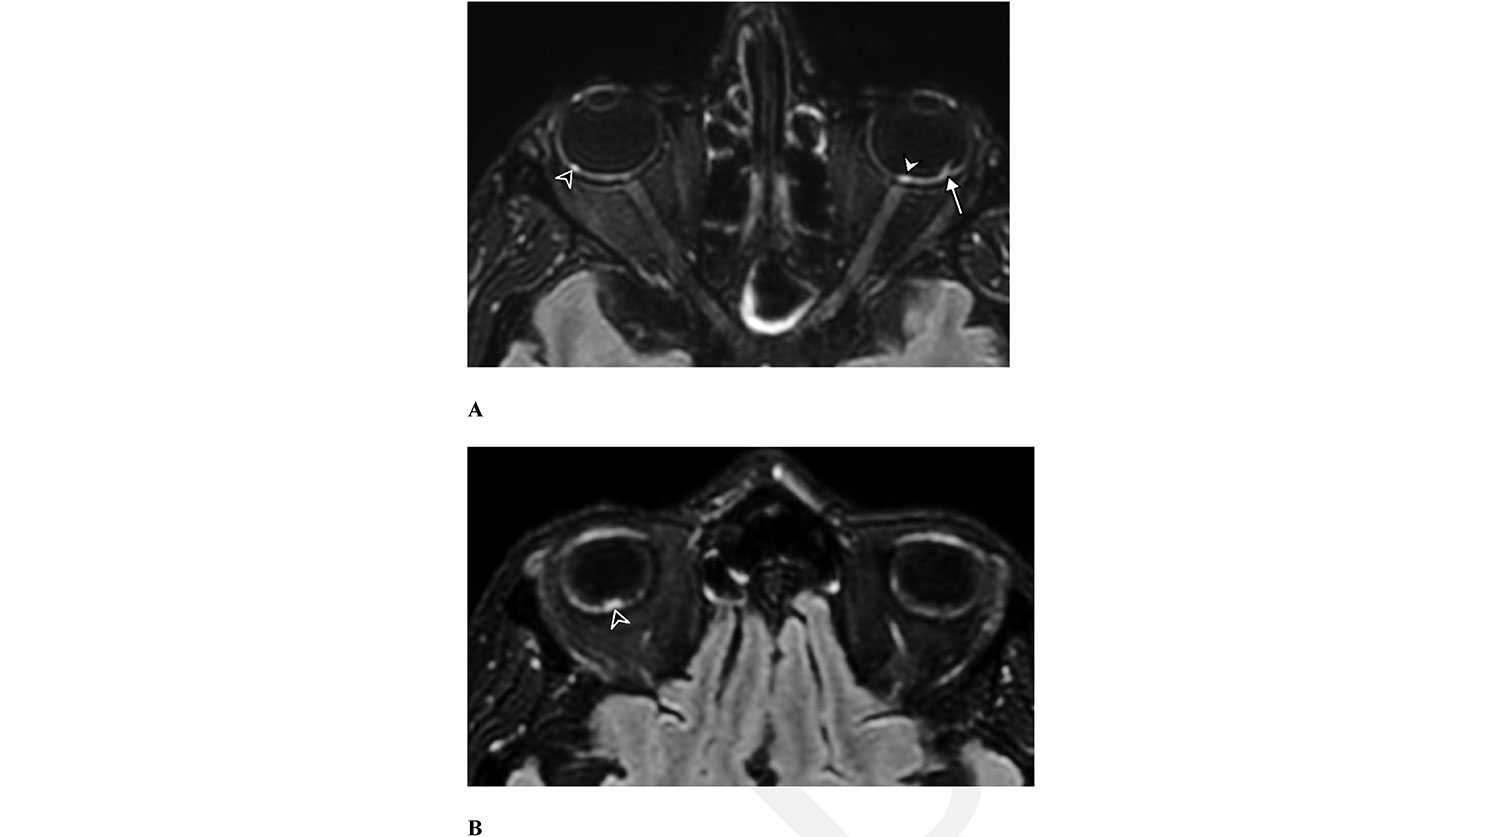

Ученые провели МРТ головы 129 пациентам, перенесшим COVID-19. У девяти из них исследователи обнаружили странные новообразования в задней части глазных яблок. Восемь из этих пациентов болели в тяжелой форме и какое-то время провели в отделении интенсивной терапии.

Хотя ранее уже сообщалось, что COVID-19 может приводить к вирусному конъюнктивиту, теперь речь идет о поражении другой части глаза, отмечают исследователи. Это затрудняет изучение узелков — рассмотреть их напрямую неинвазивно не получится. Поэтому назвать точную причину их появления пока что тоже нельзя. Однако у авторов работы есть несколько версий.